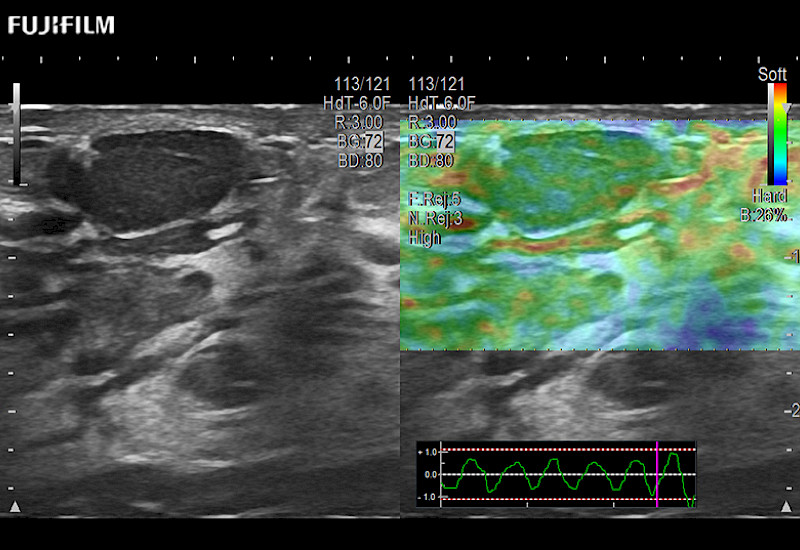

The ARIETTA 750 incorporates all of the proven technologies and functions that medical professionals have come to expect from Fujifilm Healthcare.

ARIETTA 750 is the definitive diagnostic ultrasound solution for any clinical setting - Private Office, Imaging Center, or Hospital. The ARIETTA platform provides the ultimate in clinical performance with its state-of-the-art features and large user-friendly display.

The ARIETTA 650 DI combines trusted Fujifilm Healthcare technologies and features tailored for surgical oncology.

Designed to meet the demands of surgeons, the ARIETTA 650 DI offers precise guidance. Its advanced capabilities and large, intuitive display offer accurate and efficient care in operating rooms and specialized surgical settings.